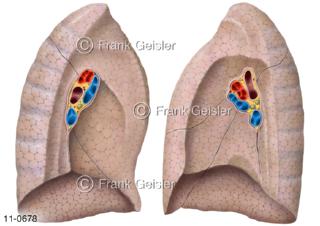

11-0678 Atemtrakt Lungen, Innenfläche der rechten und linken Lunge